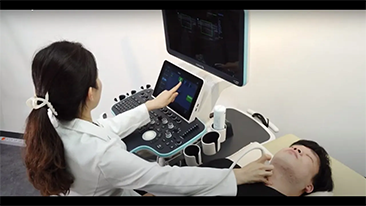

Desde que se fundó la compa?ía, Mindray ha explorado incansablemente nuevas formas de mejorar la confiabilidad del diagnóstico. Con la revolucionaria tecnología de ZONE Sonography?, la nueva plataforma ZST+ de Resona?7 lleva la calidad de la imagen por ecografía a un nivel superior mediante el procesamiento de datos de canal y la adquisición de zona.

Además de la calidad de imagen de primer nivel, Resona?7 también mejora las capacidades de investigación clínica con el revolucionario V?Flow para la evaluación hemodinámica vascular y con la adquisición de planos más inteligente a partir de conjuntos de datos 3D para el diagnóstico del SNC fetal. Al combinar el funcionamiento multitáctil basado en gestos más intuitivo y todas las características clínicas esenciales, Resona?7 realmente lidera las novedades en innovación de ecografías.